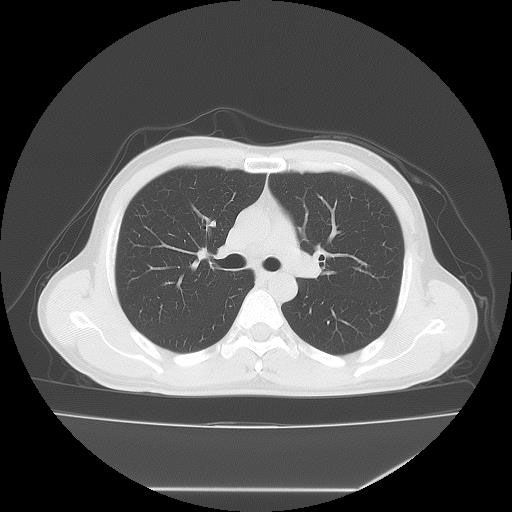

CT検査は様々な方向からX線を当て体内の水分や骨、空気など成分の違いを区別して画像を生成することで、レントゲン等では得ることができない臓器の状態を詳細に把握することが可能となり、小さい腫瘍などをより明確に映し出すことができます。

また、多角的に体内の断面図を得ることができるため立体的に構造を理解することが可能になり、病変の位置や広がりをより詳細に判断することが可能になります。

CT装置は列数が多くなると一度に広範囲の撮影が可能となり、息止め時間が短くなるため少ない負担で検査を受けて頂けます。また、より細かい断層(輪切り)画像を撮る事ができ、病変の抽出能が上がることは早期発見に繋がります。